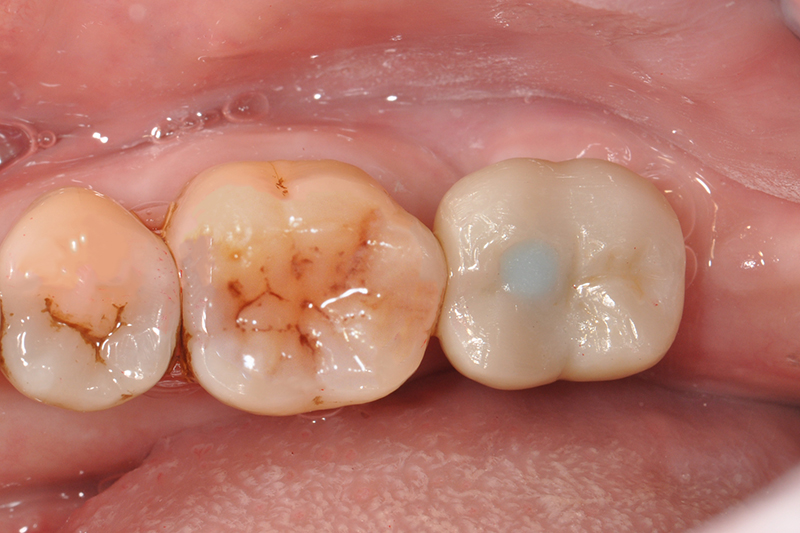

缺牙多顆

案例一

術前